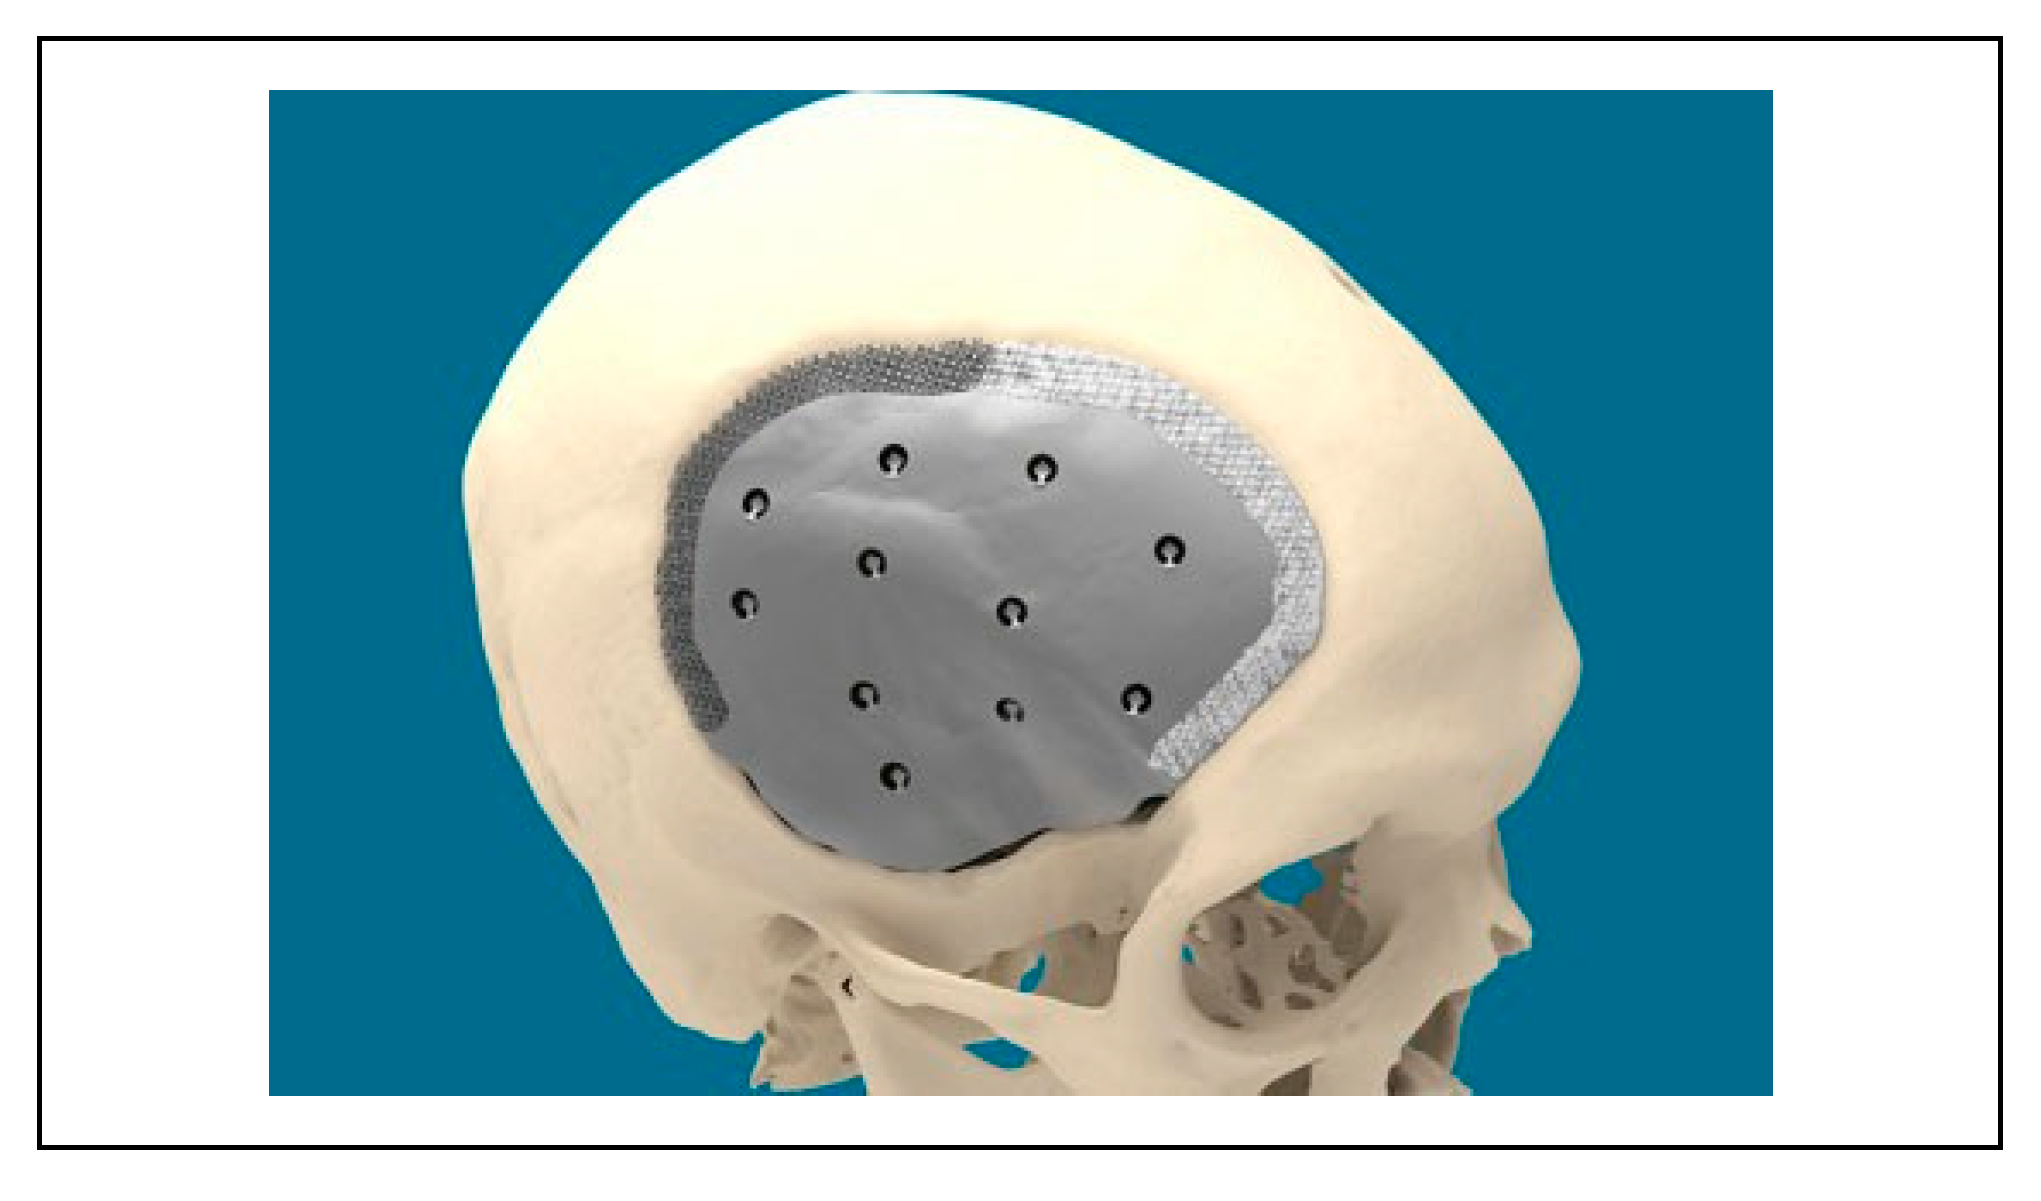

Ceramic 3D-Printed Titanium Cranioplasty

:Introduction

Case Material

Technical Aspects